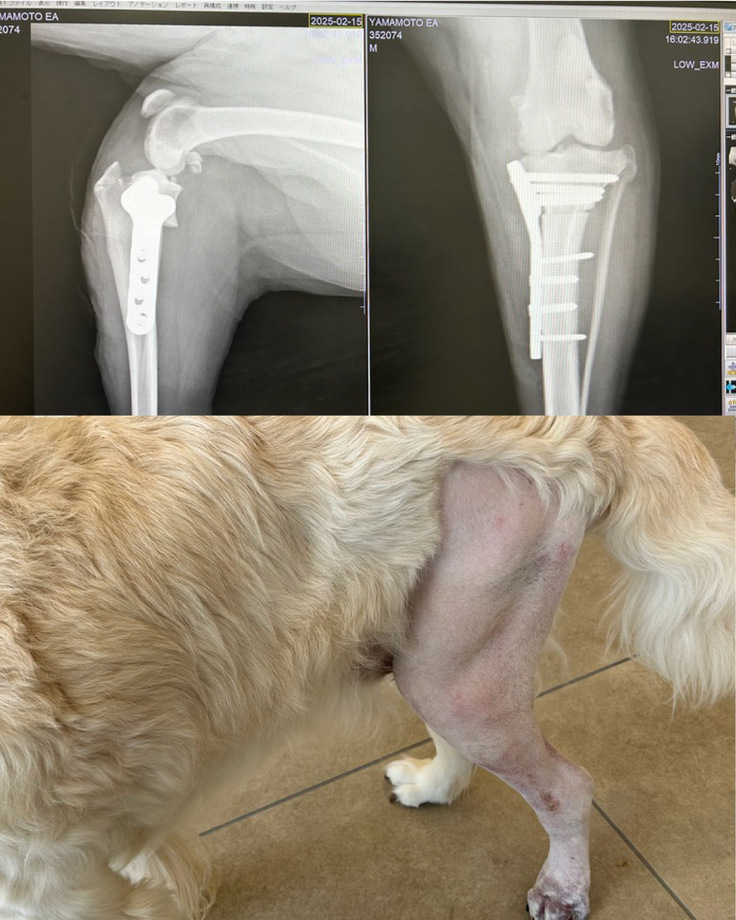

エアの状態ですが、、、

エアは長い間歩いてないので足が痩せ細っていますが少しずつ歩けるようにはなっています。歳をとって来ているのでどこまで回復できるのか気になります。

2月、術後すぐ。

術後1週間くらいなのでパンパンだし。今となっては、立ってるのが今となっては逆にすごいと思えます。足はついてるだけで体重はかかってません。

術後2週間くらい。

腫れが引いて毛が生えています。着足もできていて歩行もできます。